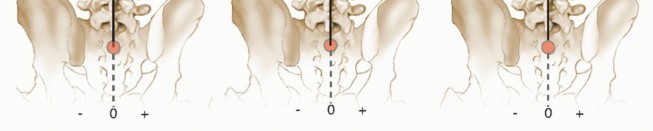

The apical vertebrae (most laterally deviated; FIG 5A)

The stable vertebra (caudal vertebra that is transected by the z-axis; FIG 5B) Rotary and lateral listhesis

FIG 5 • A. The apical vertebra is defined as that which is most deviated laterally on the PA radiograph. B. The stable vertebra is defined as the caudal vertebra that is transected by the vertical plumb line extending from the center of S1 on the standing PA radiograph. CSVL, center sacral vertical line.

FIG 5 • A. The apical vertebra is defined as that which is most deviated laterally on the PA radiograph. B. The stable vertebra is defined as the caudal vertebra that is transected by the vertical plumb line extending from the center of S1 on the standing PA radiograph. CSVL, center sacral vertical line.